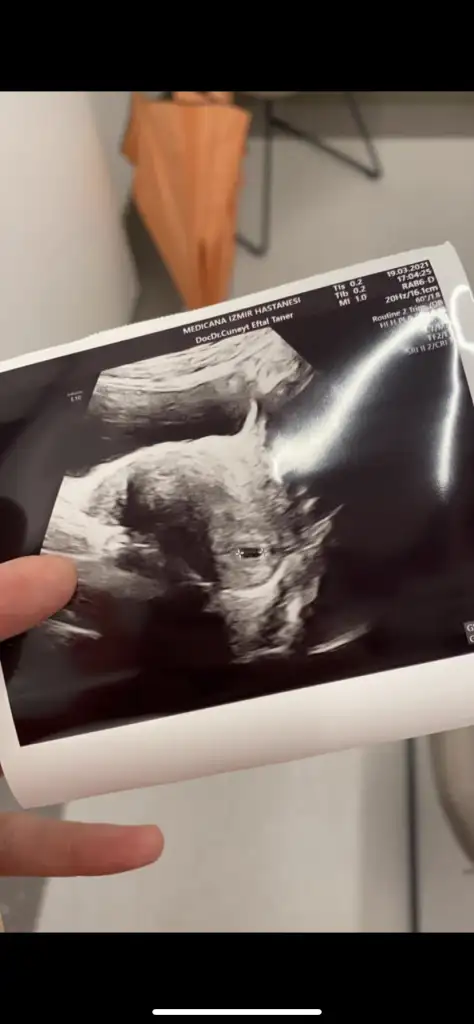

dr soylemeden siz gorun genital nub teorisi ( bebegin cinsiyeti)

Kız görünüyor